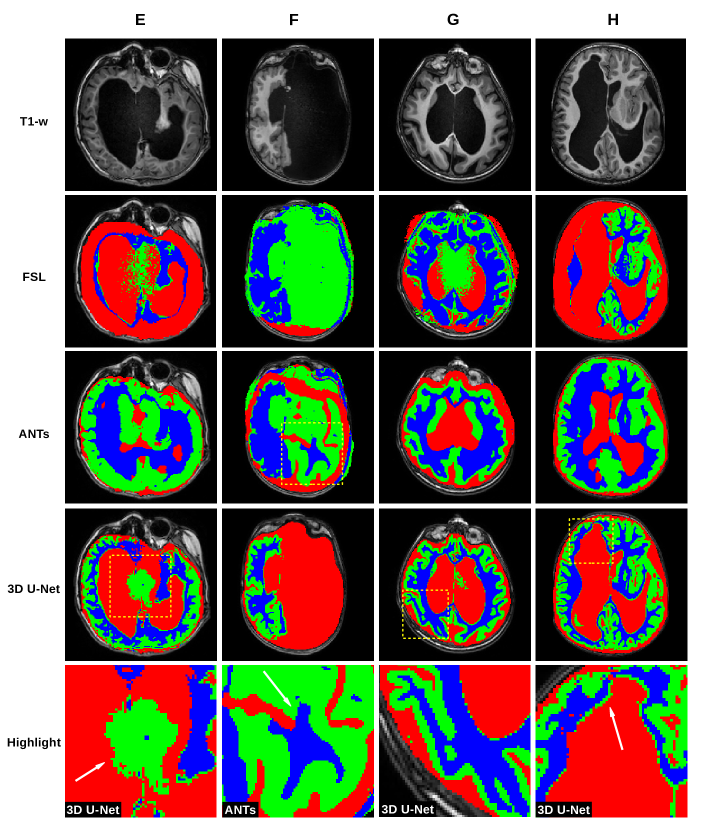

In Figure 1, we show a paradigmatic set of axial slices segmented by FSL, ANTs and the 3D U-Net, from patients with ACC, i.e. from 4 of the 12 subjects described in Section 2.2. Similarly, in Figure 2, we report paradigmatic axial slices segmented by those methods, from 4 of the subjects with complex cerebral distortions. For the segmentations of all methods, we re-labeled as CSF all the voxels inside the brain mask of each patient that were incorrectly segmented as background. In both figures in the last row, for each subject, we highlight a detail of the slice for one of the segmentation methods (indicated with a dashed square, above in the same column). Such details are discussed in Section 5.

Figure 1: First row: T1-weighted MR images of 4 subjects (A, B, C and D) with agenesis of corpus callosum. Below, the related tissue segmentations (GM in green, WM in blue and CSF in red) of the following pipelines: FSL (2nd row), ANTs (3rd row) and 3D U-Net (4th row). In the 5th row, for each subject, we show the enlarged view of one of the segmentations, indicated above with a dashed yellow square. White arrows point to the highlights discussed in Section 5.

Figure 1 shows that FSL fails to segment GM and WM in cases of moderate and severe ventricular dilatation with thinning of the WM (case A, C and less evident in D). In one case (B) FSL also misses identifying the thalami as (deep) GM. ANTs performs better in identifying (deep) GM and the cortex at the convexity. However, case A and C show that it may fail in differentiate between GM and subcortical WM on the mesial surface of the hemispheres. This may be related to the prior used by that pipeline, which is based on the anatomy of normal subjects and not designed to recognize spatial reorganization of the cortex, especially in the midline, like in ACC cases. A similar error is in case C where a cortical component close to the head of the caudate is misclassified as WM. Finally in D, Probst bundles, which are abnormal WM tracts running parallel to the medial ventricular wall, are labelled as GM. In contrast, the 3D U-Net performs well in segmenting ACC. The most relevant error in these cases is at the interface between ventricles and WM: the 3D U-Net wrongly identifies a very thin layer of GM along the inner ventricular surface. This is probably related to partial volume effects.